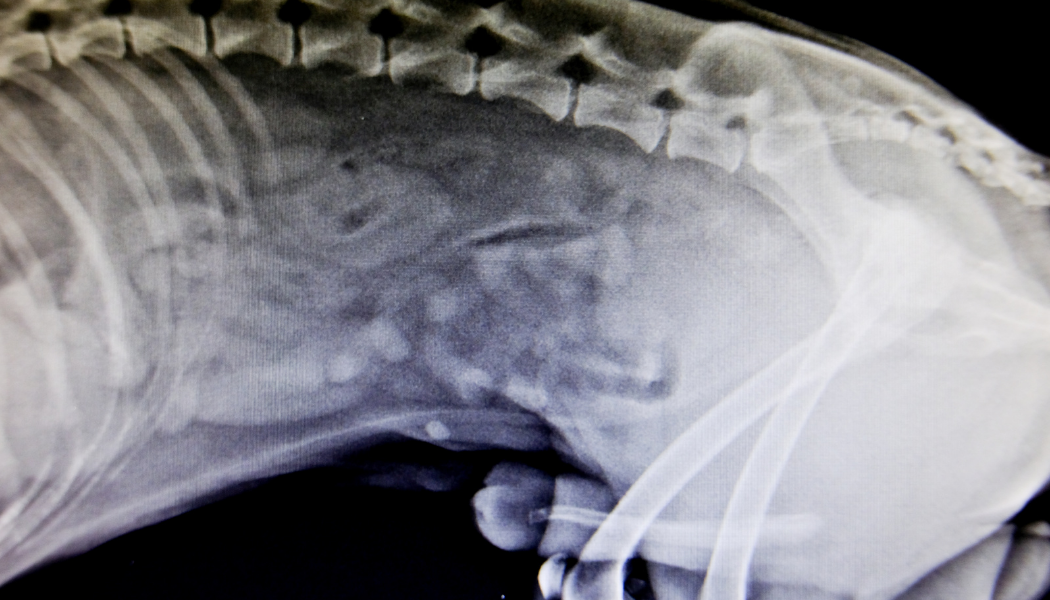

Whether you are interested in orthopaedics or not, fractures and trauma commonly present in general practice, and there are often many decisions and steps to make before even thinking about surgery and implants. This lecture will cover the initial triage and stabilisation, diagnosis and management of these cases, which range from simple one bone fractures to complex polytraumas, potentially with associated soft-tissue wounds or open fractures. At each stage, there are many different decisions to make, and different options available. This lecture will help you navigate the decision making around analgesics and antibiotics, give tips and tricks for getting the best out of your radiographic workup, work through initial wound management and overview temporary stabilisation prior to surgery. Finally, we will discuss when fractures can be managed conservatively or with coaptation, which candidates are best managed surgically, and how soon does surgery need to happen, and what the surgical options are.